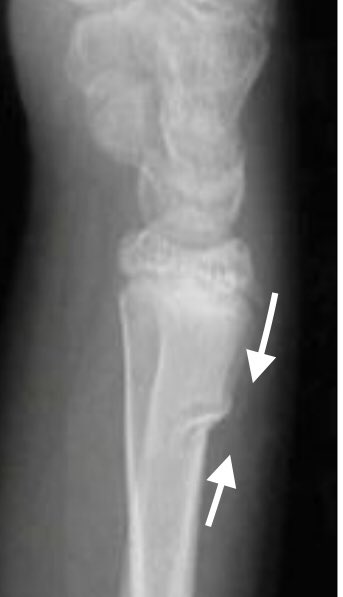

A Buckle (or Torus) fracture of the distal radius in a child - failure in compression of the dorsal cortex - a stable common injury : @AOUKEd @KidsRbh #forcetrial